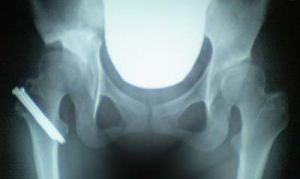

■いくらスペシャルヌード画像(レントゲン

の写真とも言う)

またデジカメ忘れて携帯で撮影。

骨に埋まっているボルト2本を抜く手術が必要で来月に予約をいれました。

ボルトを抜いたほうが筋トレがスムーズにいくんだとか。

すごいはっきりボルトが見える~!!ヽ(・_・;)ノ